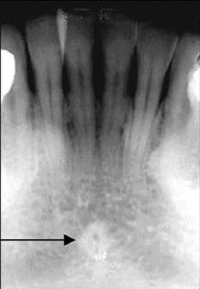

65. What is the anatomical structure indicated by arrow in this radiograph?

Incisive Foramen ( Nasalpalatine or anterior palatine foramen ) -The oral terminus of the nasalpalatine canal. - projected b/w roots and region of the middle and apical thirds of the central incisors. -potential site for cyst formation. - Presence of a cyst is predumed if the width of the foramen exceeds 1 cm.